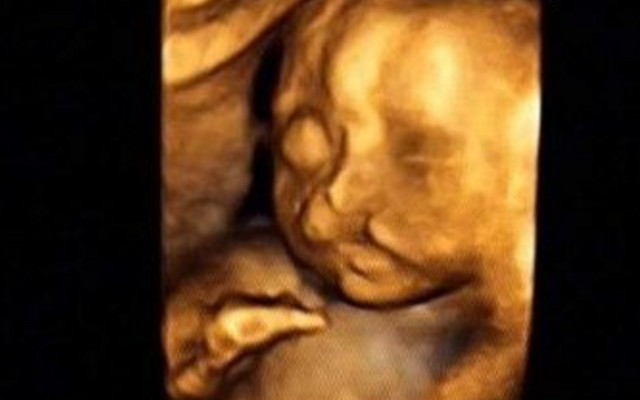

30岁的小孙就有唇裂,修补过的疤痕仍很分明。在最近一次三维B超显示,腹中的胎儿居然中度唇裂。她通知大夫,由于她诞生就有唇裂,小时老是被讪笑和厌弃。所有,无论怎样也要流掉腹中的宝宝,她不想让她的孩子再经历这样的经历。

大夫却通知小孙,现在已经孕21周,如果引产对身材损伤十分大,如果在次怀孕,不能包证就不会得唇腭裂,第二次仍会怀上唇腭裂宝宝的几率约为4%,假如怀过两次唇腭裂的宝宝,第三次怀上唇腭裂宝宝的几率会提升到14%。如今婴儿唇腭裂整形手艺,已经十分胜利,即使是重度的唇腭裂,仍是能够修补得简直看不出来了。倡议把孩子生上去,不要由于这点瑕疵,就将宝宝的性命闭幕。